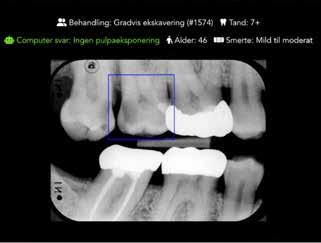

I et igangværende samarbejde mellem Odontologisk Institut samt Institut for Computer Science, Københavns Universitet, indgår AI bl.a. i et projekt (30) til at bistå vurderingen af det forventede resultat efter ekskavering af et dybt cariesangreb. Vil der komme pulpaperforation eller ej? Den aktuelle algoritme er ”oplært” på baggrund af et datasæt bestående af faktiske behandlinger udført i Skandinavien. I korte træk kan algoritmen efter at have analyseret et aktuelt røntgenbillede på computerskærmen med en operativ krævende carieslæsion kunne foreslå det forventede resultat, såfremt der udføres fx en gradvis

ekskavering (Fig. 7). Præliminære resultater viser, at metoden endnu er for usikker, til trods for at den pågældende algoritme er forholdsvis god til at forudsige, om der rent faktisk kom perforation til pulpa eller ej ved en specifik ekskaveringsmetode. Det er derfor nødvendigt at ”træne” algoritmen yderligere, hvis den fulde effekt af AI skal have sin indflydelse i denne sammenhæng. Et andet interessant aspekt i undersøgelsen var, at i de tilfælde, hvor algoritmens forslag til behandlingsresultatet ikke blev fulgt, var den vurdering, der blev valgt, ofte mere invasiv end den egentlige behandling viste. Med andre ord forsøgte algoritmen at forebygge overbehandling. Endelig er det vigtigt at bemærke, at AI ikke af sig selv opdateres på baggrund af relevante nye forskningsresultater, medmindre algorit-

AI perforationsprædiktion

Fig. 7. Et eksempel på en test-bruger-flade, der viser et aktuelt røntgenbillede, hvor en AI model foretager en prædiktion af pulpaperforation af 7+, hvis en given behandling udføres (computersvar). Der oplyses tillige om patientens alder (46 år), samt om der har været smerter eller ej. Aktuelt forventes ikke pulpaeksponering (ingen pulpaeksponering), hvis der foretages gradvis ekskavering på 7+. Som bruger kan man så vælge, om man er enig eller ej i computerens anbefaling.

Fig. 7. An example of a test user-interface showing a current radiograph where an AI model makes a prediction of pulp exposure of 7+ if a given treatment is performed (computer response). Information is given about the patient’s age (46 years) and whether there has been pain or not. Currently, no pulp exposure is expected if stepwise excavation is performed (7+). As a user, you can then choose whether you agree or not with the computer's recommendation.